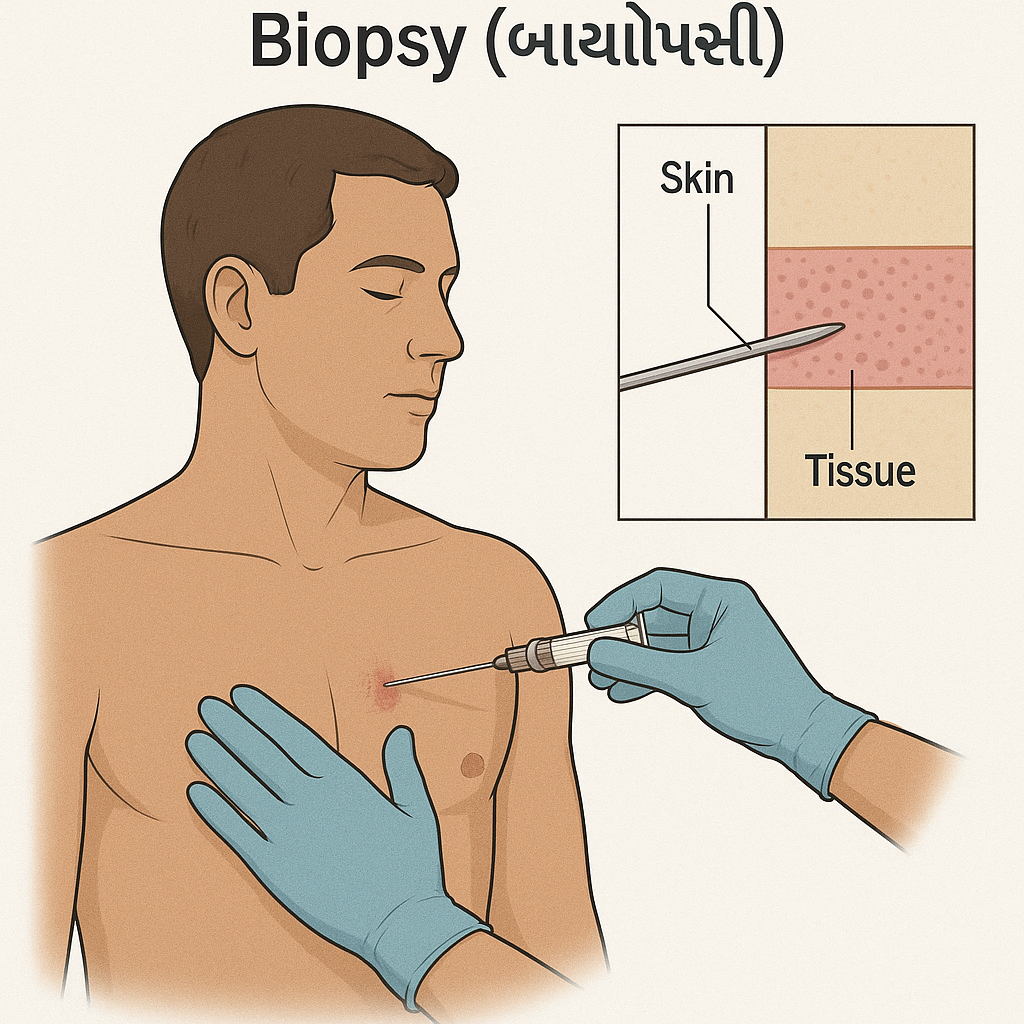

Biopsy (બાયોપ્સી):

- બાયોપ્સીમાં સસ્પેક્ટેડ એરિયામાંથી ટીશ્યુનું સ્મોલ સેમ્પલ કલેક્ટ કરવામાં આવે છે અને તેનું માઇક્રોસ્કોપિક એક્ઝામિનેશન કરવામાં આવે છે. જેથી તેમાં મેલીગનન્સી પ્રેઝન્ટ છે કે નહીં તે આઇડેન્ટીફાય કરી શકાય.

Pleural biopsy (પ્લુરલ બાયોપ્સી):

- પ્લુરલ બાયોપ્સીમાં પ્લુરામાંથી ટીસ્યુનું સ્મોલ સેમ્પલ કલેક્ટ કરવામાં આવે છે.

(લંગ અને ચેસ્ટ કેવીટીની આજુબાજુ આવેલ થીન મેમ્બ્રેનને પ્લુરા તરીકે ઓળખવામાં આવે છે). - પ્લુરલ બાયોપ્સી એ નીડલ બાયોપ્સી અથવા થોરાકોસ્કોપીની મદદથી કલેક્ટ કરવામાં આવે છે.

Lung biopsy (લંગ બાયોપ્સી):

- લંગ બાયોપ્સીમાં લંગ્સમાંથી લંગ ટીસ્યુનું સેમ્પલ કલેક્ટ કરવામાં આવે છે અને તેનું એક્ઝામિનેશન કરવામાં આવે છે. જેથી લંગ કેન્સર, લંગ ઇન્ફેક્શન અને ડીઝીસને આઇડેન્ટીફાય કરી શકાય છે.

લંગ બાયોપ્સી કલેક્ટ કરવા માટે જુદી જુદી મેથડ નો ઉપયોગ કરવામાં આવે છે:

- બ્રોન્કોસ્કોપિક બાયોપ્સી (Bronchoscopic biopsy)

- ઓપન લંગ બાયોપ્સી (Open lung biopsy)

- મેડિયાસ્ટીનોસ્કોપી (Mediastinoscopy)

- નીડલ બાયોપ્સી (Needle biopsy)